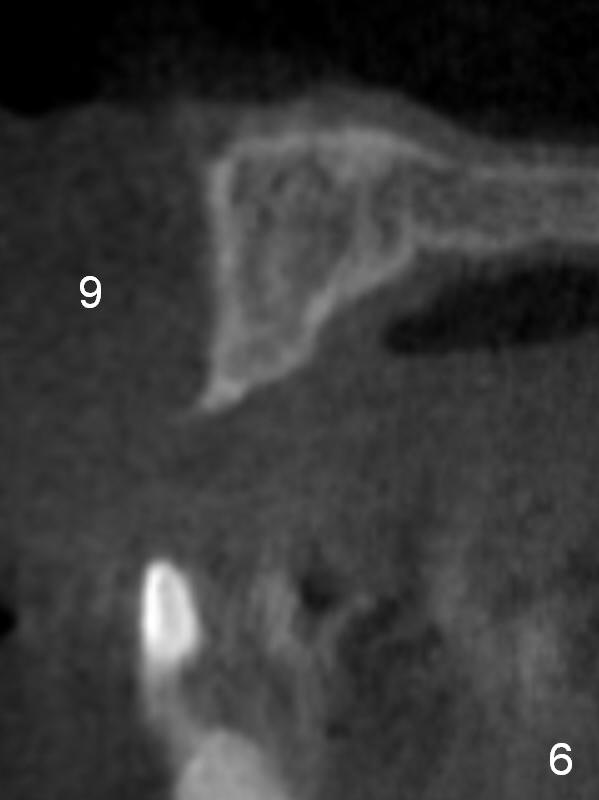

After implant reconstruction of the lower right and left (including #19) regions, the same treatment is considered in the atrophic anterior maxilla (#8-13) for anchorage for upper left molar cross bite correction. The smallest implants are to be placed in the each of the sites with different strategies. For example, at the site of #8 (Fig,1,2), ridge split with wheel (Fig.3) and microsteotomes (Fig.4) are used to place 1-piece implant (3x14 mm). The site of #9 has a pointed ridge and a wide base (Fig.6); a 1-piece angled implant (3x14 mm 15 °) is placed palatally (Fig.7). The ridge and base at #10 are narrow (Fig.8); after truncating the pointed ridge, a 2.0 or 2.5 mm 1-piece implant is placed parallel to the palatal wall (Fig.9).